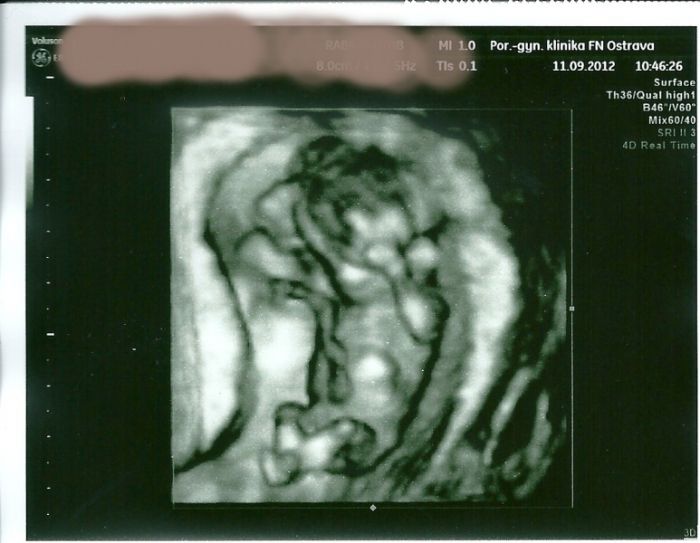

Ještě jedna rozmazaná první od prcka, poprvé jsem si řekla o foto

. Nic moc to není na živo to je lepší, ale vy víte, že?